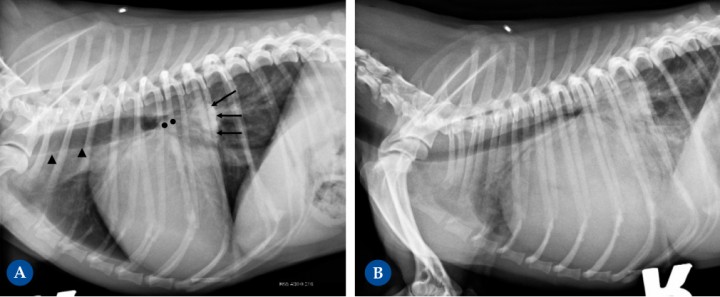

West Highland White Terrier macho castrado de 14 años presentado por tos crónica. En la proyección lateral derecha (Fig. 3A), la silueta cardíaca está aumentada de tamaño, ocupando 4 espacios intercostales (ref<2,5-3), produciendo un desplazamiento dorsal de la tráquea, adquiriendo una posición paralela respecto a la columna vertebral (flechas negras punteadas). El aumento del apoyo esternal en la vista lateral y apariencia de D invertida en la proyección DV de la Fig. 3B (mayor engrosamiento con una forma más redondeada, flechas blancas) son consistentes con cardiomegalia derecha. El cuadrante craneodorsal amplio está causado por dilatación del atrio derecho. Considerando la raza y los cambios en el parénquima pulmonar asociados, con un aumento de la opacidad pulmonar con áreas de patrón alveolointersticial, más marcado en lóbulos caudodorsales (cabezas de flecha) compatibles con posible fibrosis pulmonar, los cambios cardíacos son compatibles con un cor pulmonale por hipertensión pulmonar secundaria a la enfermedad respiratoria, afectando predominantemente al corazón derecho. También se detecta redundancia de la membrana dorsal de la tráquea (flechas negras), sugestivo pero no diagnóstico de colapso de tráquea.

Perro mestizo macho castrado de 12 años presentado para la investigación de soplo cardíaco debido a enfermedad degenerativa de la válvula mitral. La radiografía de la Fig. 4A (proyección lateral derecha) muestra cardiomegalia evidente, con un aumento severo del cuadrante caudodorsal, correspondiente con la dilatación marcada del atrio izquierdo (flechas negras). Esta causa elevación de la tráquea (paralela a la columna vertebral, cabezas de flecha negra) con compresión bronquial (puntos negros) debido al aumento de tamaño del atrio izquierdo. Ambos ventrículos están incrementados de tamaño, resultando en una silueta cardíaca que ocupa aproximadamente 3,5 espacios intercostales (ref<2,5-3). La presencia de leve patrón intersticial dorsocaudal hace sospechar de fases iniciales de insuficiencia cardíaca congestiva izquierda. La radiografía de la Fig. 4B (proyección lateral derecha) corresponde al mismo paciente, mostrando progresión severa de la enfermedad, ahora en fase terminal. Muestra marcada cardiomegalia generalizada, con la silueta cardíaca ocupando unos 4 EIC, con marcado desplazamiento dorsal de la tráquea y con compresión de los bronquios. También se detecta un patrón pulmonar intersticial generalizado con áreas de marcado aumento de la opacidad pulmonar (patrón alveolar), correspondiente a edema pulmonar cardiogénico marcado, signo de insuficiencia cardíaca izquierda.